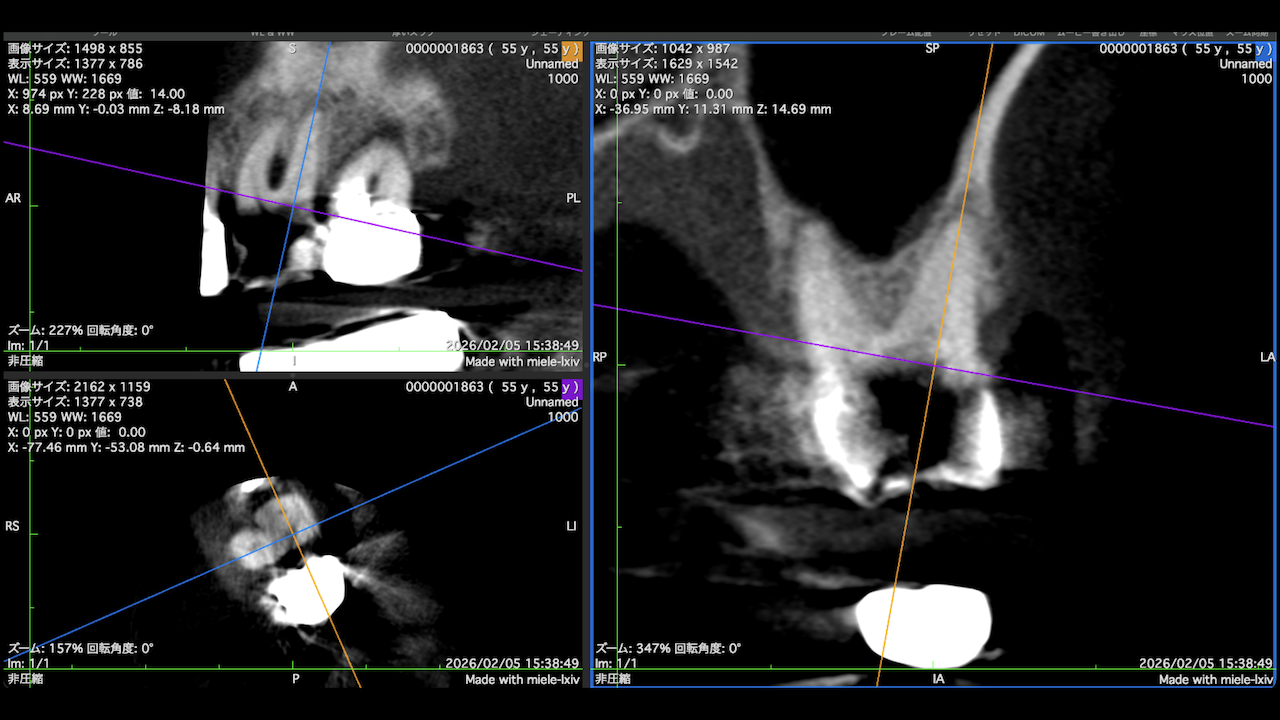

術前にCBCTを撮影したので、MB2がないということを分かった上で根管治療を行っている。

これがCBCTを歯内療法に用いる最大の利点だろう。

上手い!